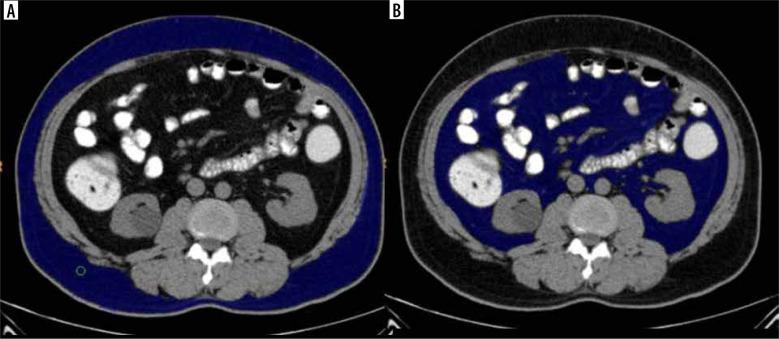

Abdominal obesity plays a significant role in the development of metabolic syndrome, with individual metabolic risk profiles for visceral and subcutaneous adipose tissues. This study aimed to calculate and correlate the subcutaneous, visceral, and total fat compartment volume in metabolic and non-metabolic syndrome patients.

MATERIAL AND METHODS

This was a cross-sectional study conducted on 112 patients categorized into Group A (with metabolic syndrome) and Group B (without metabolic syndrome). They were subjected to computed tomography (CT) study of the abdomen using a 128-slice MDCT scanner. Body mass index (BMI), visceral fat volume (VFV), subcutaneous fat volume (SFV), and total fat volume (TFV) were calculated and correlated with biochemical evidence of metabolic syndrome.

腹部肥胖在代谢综合征的发展中起重要作用,内脏和皮下脂肪组织具有个体代谢风险特征。本研究旨在计算代谢综合征患者和非代谢综合征患者的皮下、内脏和总脂肪腔室体积,并进行相关性分析。

材料与方法

这是一项横断面研究,对112例患者进行了分组,分为A组(患有代谢综合征)和B组(未患有代谢综合征)。使用128层MDCT扫描仪对他们进行腹部计算机断层扫描(CT)研究。计算体重指数(BMI)、内脏脂肪体积(VFV)、皮下脂肪体积(SFV)和总脂肪体积(TFV),并与代谢综合征的生化证据进行相关性分析。